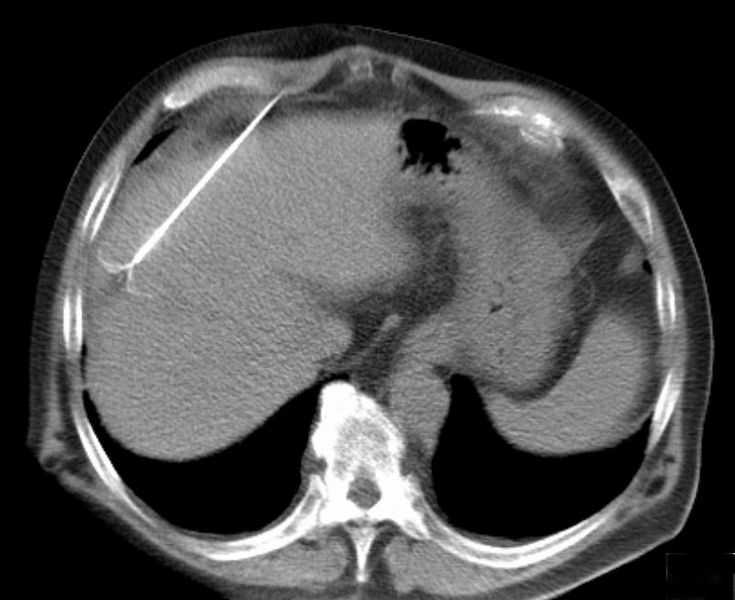

CT scan showing radiofrequency ablation of a liver lesion |

Radiofrequency ablation (RFA) is a minimally invasive treatment, one of several types of ablation therapy, where surgery is not a good option. Guided by imaging, a thin needle or probe is inserted through the skin and into the tumor.The probe passes alternating electrical current (radiofrequency energy) through the tumor tissue generating heat at the site of the tumor. This causes tumor necrosis (cell death) and destruction of cancerous tissue.The dead cells eventually turn into a harmless scar.

RFA is used to treat numerous tumors including those in the liver, bone, kidney, and lung. A key advantage is it selectively destroys cancer cells while leaving healthy cells unaffected. The size and location of tumors are a factor in whether RFA can be used.